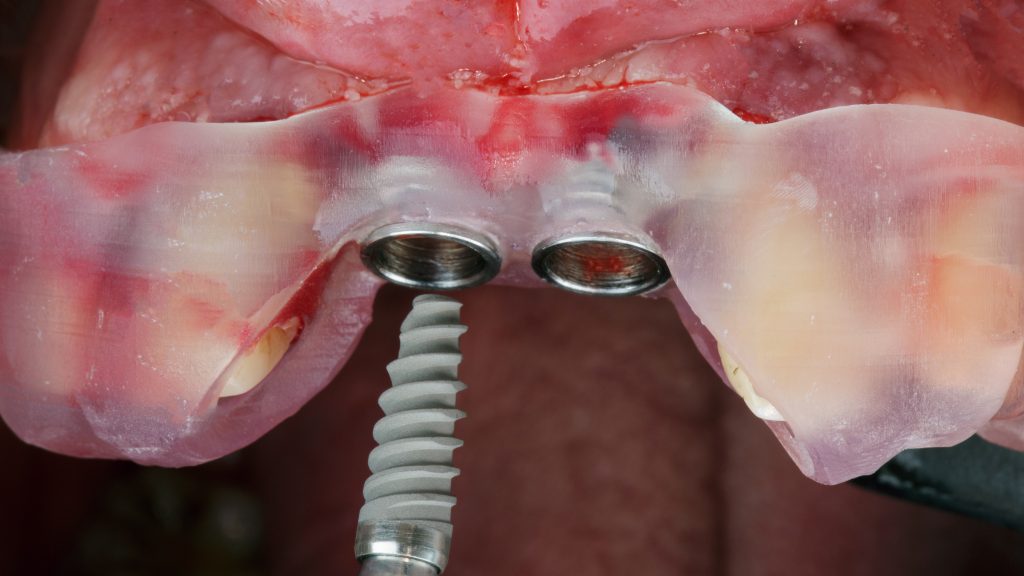

- Appréhender des cas de reconstruction ostéo-muqueuses et de mise en charge immédiates.

Le choix de votre formation en implantologie est déterminant pour votre succès.Notre ‘Institut de Formation en Implantologie et Parodontologie (IFIP) est un organisme de formation réputé qui propose des programmes alliant théorie et pratique pour une prise en charge sûre et rigoureuse de vos patients. Nos formations, construites sur un modèle innovant avec notre partenaire Blendi, sont reconnues par l’ANDPC,FIFPL, l’OPCO et la MACSF. Elles vous offrent un accompagnement personnalisé, des travaux pratiques sur modèles ou mâchoires animales, et un mentorat clinique pour vous permettre d’acquérir une totale autonomie. Avec l’IFIP, vous vous formez auprès d’experts reconnus pour faire de l’implantologie une source d’épanouissement professionnel.